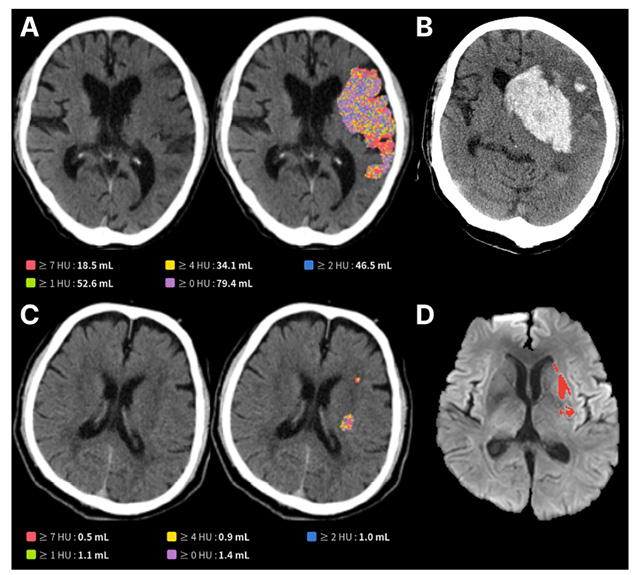

• A. JLK-CTI 예측 뇌경색 범위가 넓은 환자, B. 시술 이후 뇌출혈 발생, C. 예측 뇌경색 범위가 넓지 않은 환자, D. 시술 이후 작은 뇌경색으로 좋은 예후 /이미지 제공=제이엘케이

▲ A. JLK-CTI 예측 뇌경색 범위가 넓은 환자, B. 시술 이후 뇌출혈 발생, C. 예측 뇌경색 범위가 넓지 않은 환자, D. 시술 이후 작은 뇌경색으로 좋은 예후 /이미지 제공=제이엘케이

제이엘케이의 AI 모델은 NCCT와 확산강조영상(DWI) 데이터를 학습해 미세한 뇌 손상 영역을 자동 검출하고 부피를 정량화하도록 설계됐다. 연구팀은 국내 6개 뇌졸중 센터에서 확보한 603명 환자 데이터를 분석해 임상적 유효성을 검증했다. 그 결과, 손상 부피가 50mL를 초과할 때 3개월 후 회복 가능성이 17.3%로, 50mL 이하 환자(54.2%)보다 현저히 낮았다. 또 손상 부피가 큰 환자일수록 뇌출혈 등 합병증 발생 위험도 더 크게 나타났다. 이는 응급실 기본 영상만으로도 장기 예후를 예측할 수 있음을 보여주는 근거를 제시했다.